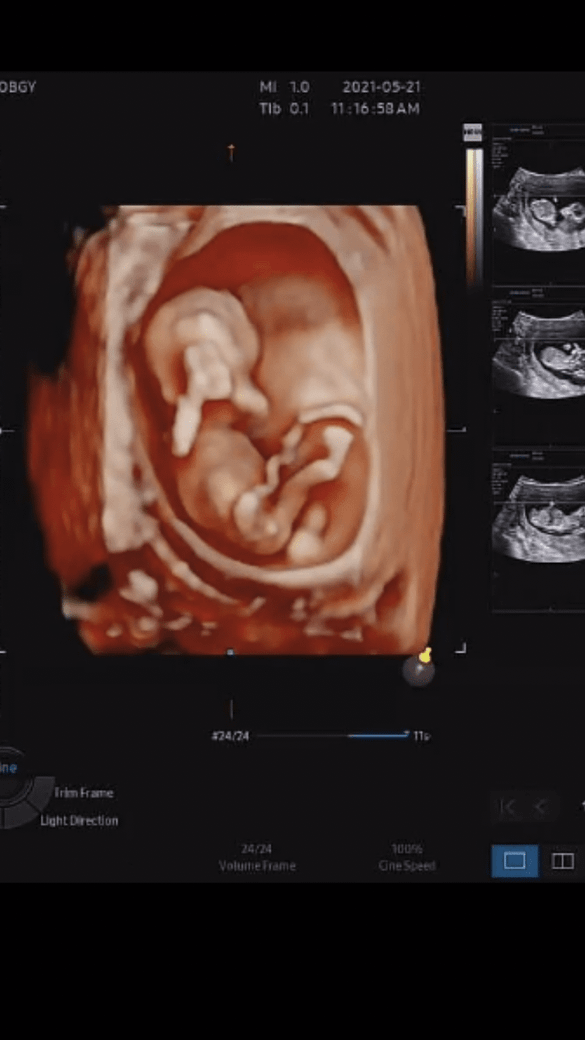

12주 오늘 입체초음파 찍고 왔는데요

아직은

남녀 성별 구분이 어렵다고들 하는데 너무 궁금해서요!

12주 시기에 남녀 둘다 튀어나와 있다곤 하는데 조금이라도 보시고확률 적으로 좀 힌트좀 주세요~~

• 1번 째 사진